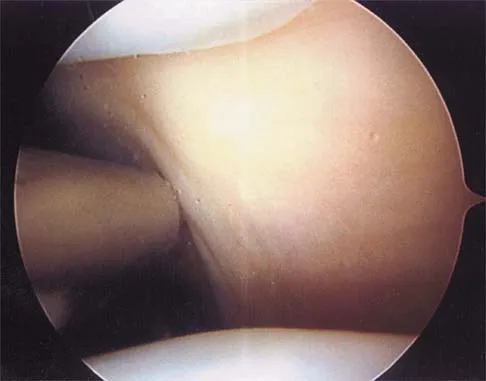

A patient has right shoulder pain. Figure 1a shows a gadolinium-enhanced transverse MRI scan at the level of the coracoid. Figure 1b shows an arthroscopic view of the anterior structures from a posterior portal. These images reveal which of the following findings?

Explanation